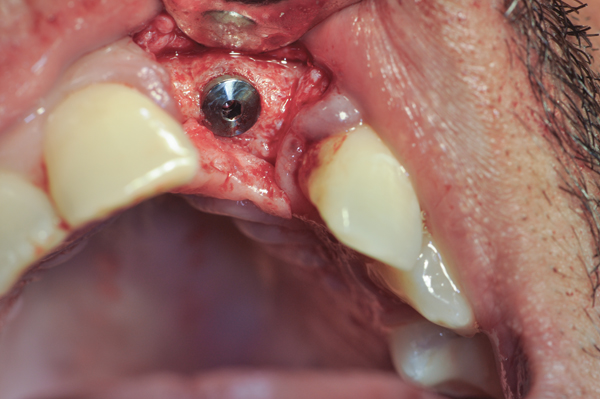

Fig 14. An implant was inserted in regenerated bone.

Figure 14